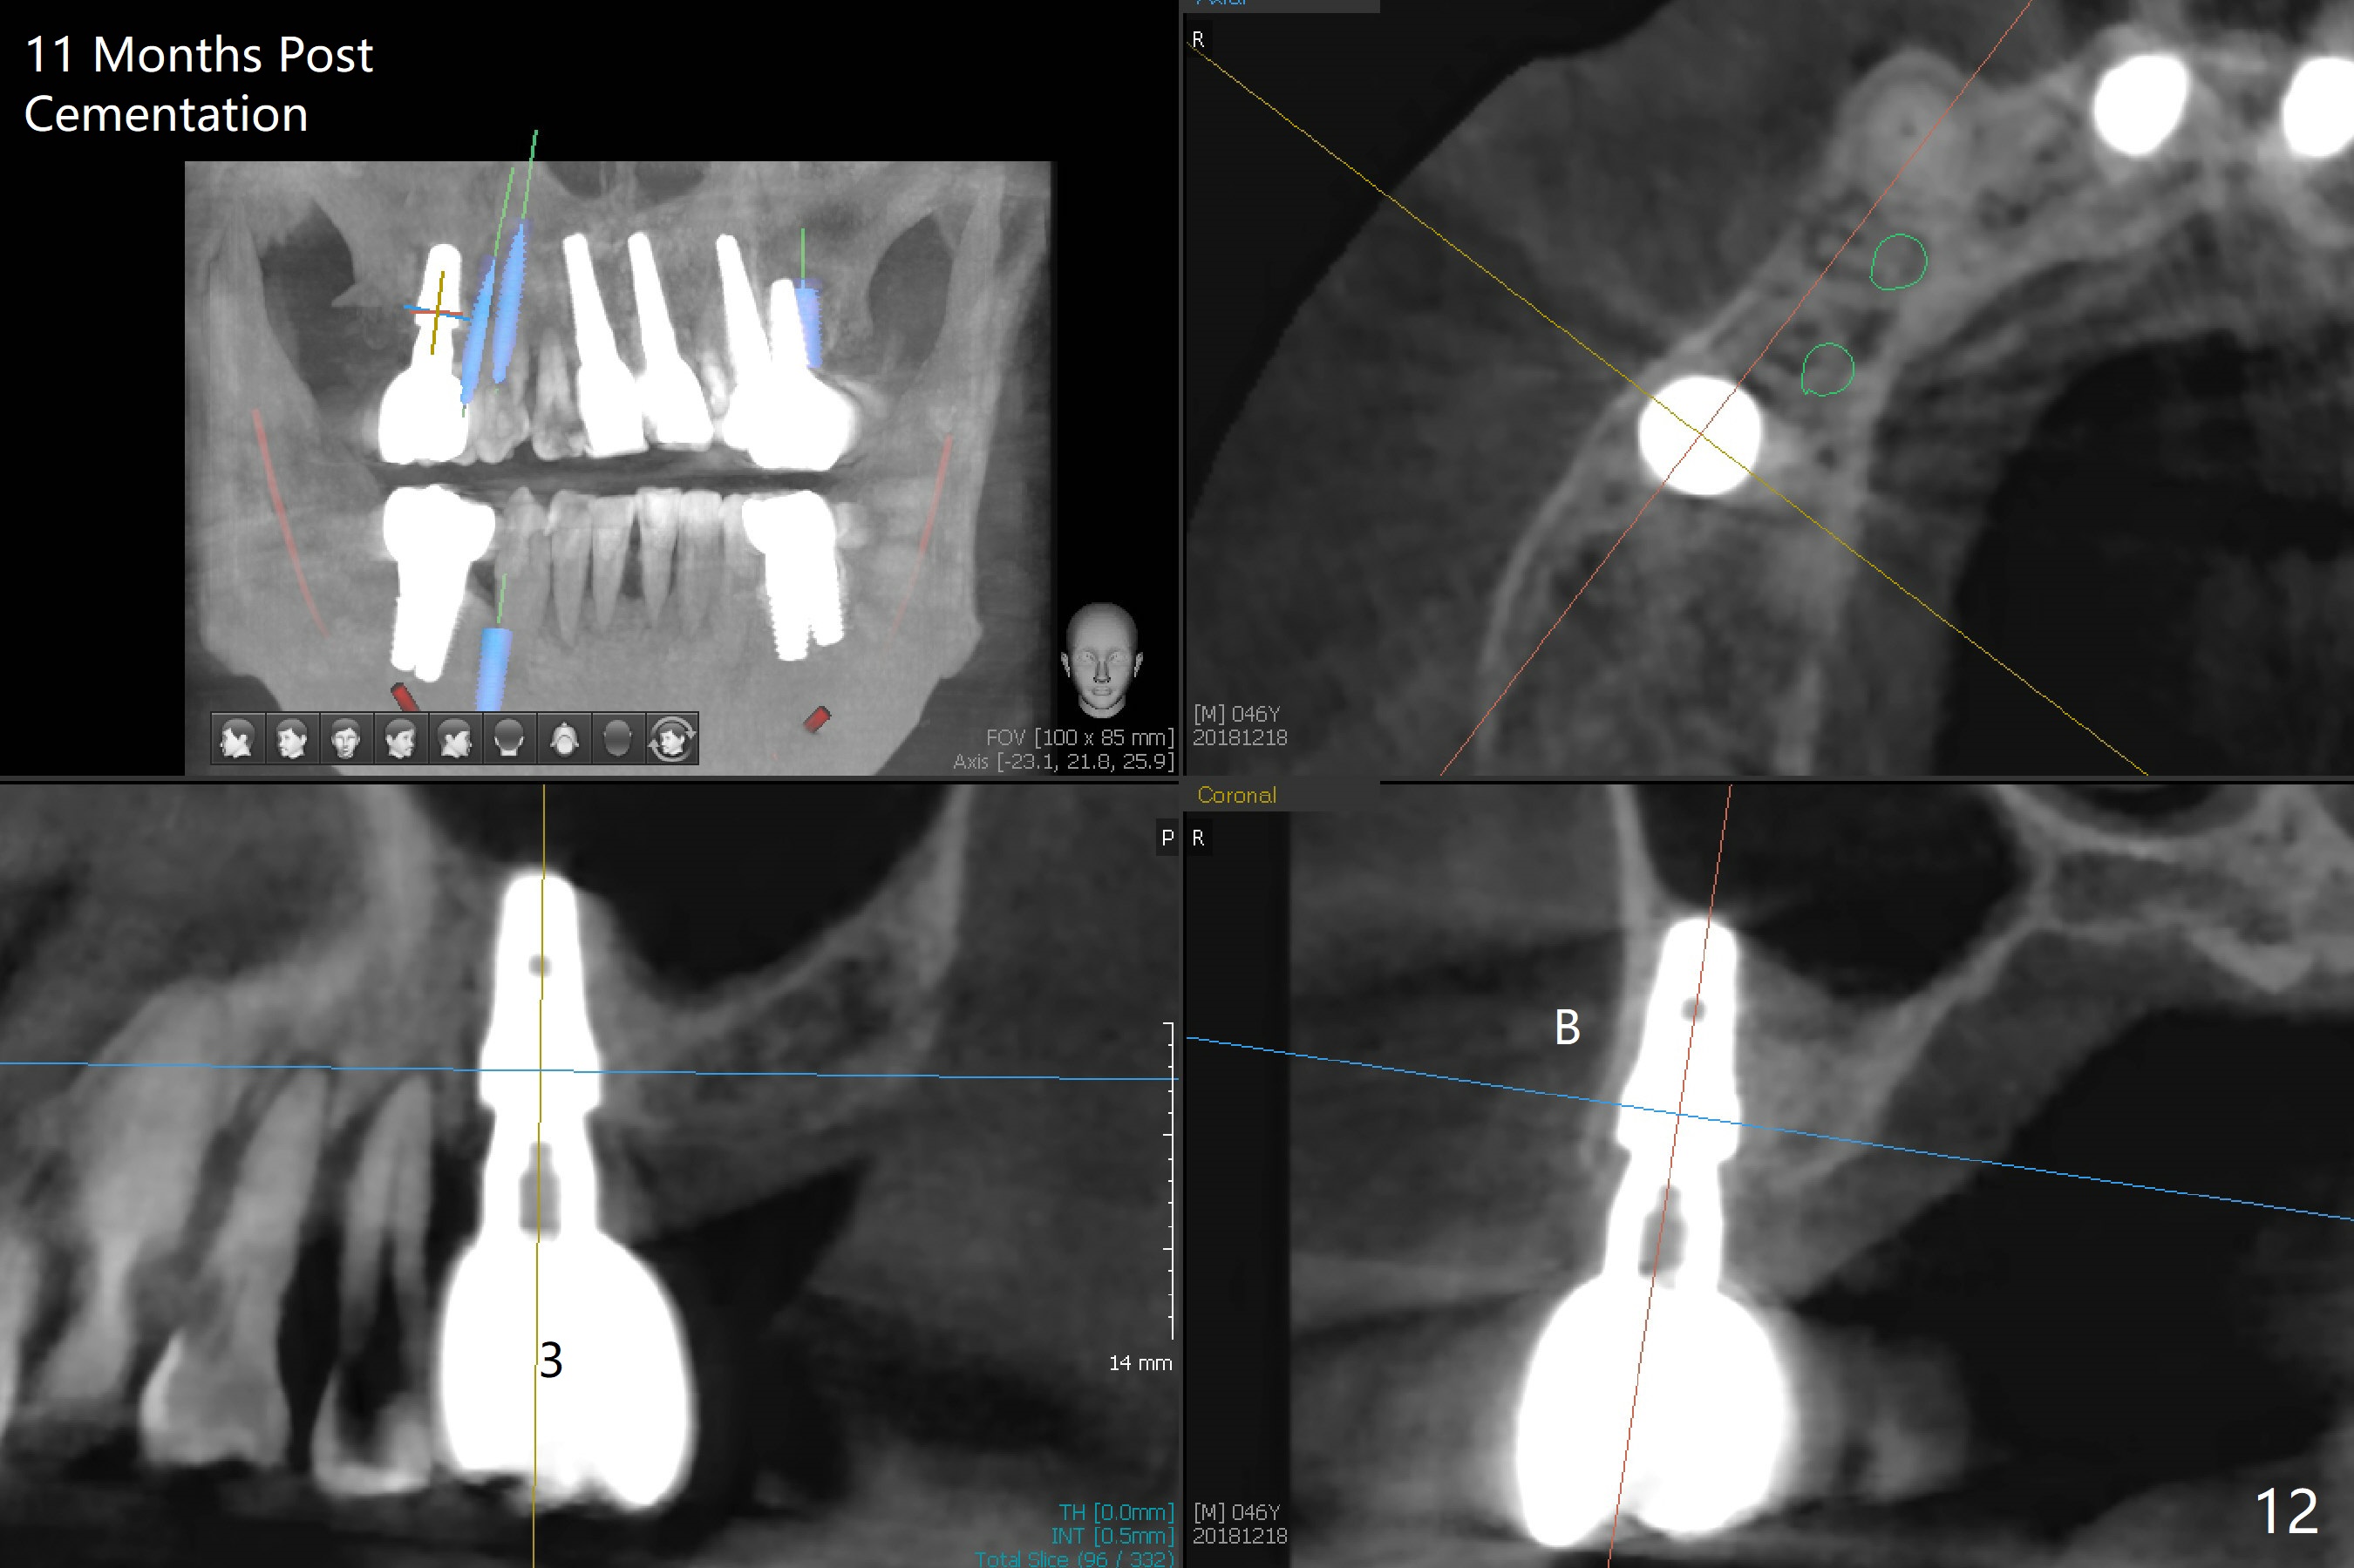

After extraction of the tooth #3 (Fig.1,2), the palatal socket (P) is as wide as the buccal one (B; Fig.3,4 (socket impression)), as compared to the roots), suggesting bone loss is more severe palatally than buccally. There is a circular area in the buccal slope of the palatal socket, in which the bone looks thin (purplish: presumably the sinus membrane underneath, Fig.5,7 (blue circle)). It appears that the palatal slope of the buccal socket (Fig.6, 7 red dashed line) is the most appropriate site for osteotomy (Fig.8). Prior to inserting 5.3 mm tap drill (Fig.9), the mesiopalatal region of the osteotomy (corresponding to the blue circle in Fig.7) perforates without sinus membrane tear. A small piece of Osteogen plug is placed in the perforation before inserting a 5.3x10 mm SM implant (Fig.10,11). Following placement of another piece of Osteogen plug in the palatal socket and of a 4.8x7(6) mm abutment, mineralized cortical and cancellous bone is placed (*). Collagen plug and an immediate provisional are used to close the socket opening. CT taken 11 months post cementation shows that the implant is placed within bony boundary, although buccally (Fig.12 B). Bone graft seems to heal in the sinus (Fig.13 (sagittal section),14 (coronal section) white * (Osteogen plug) and in the socket (brown * (allograft and Osteogen)).